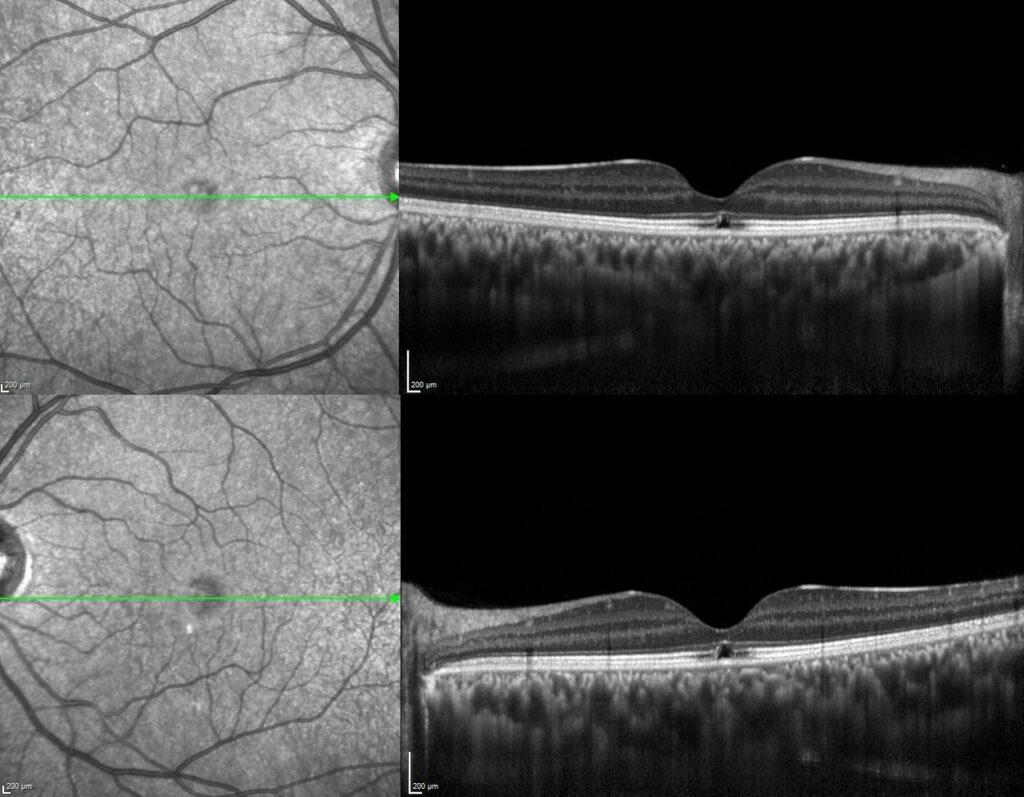

Dilated fundus examination revealed a small, yellow, round foveal lesion in both eyes. Spectral domain optical coherence tomography (SD-OCT) scans demonstrated symmetric focal disruption of the subfoveal interdigitation and elipsoid zones in addition to underlying RPE, while the rest of the internal architecture is maintained.

Credit: Kemal Tekin, M.D., from Ulucanlar Eye Training and Research Hospital